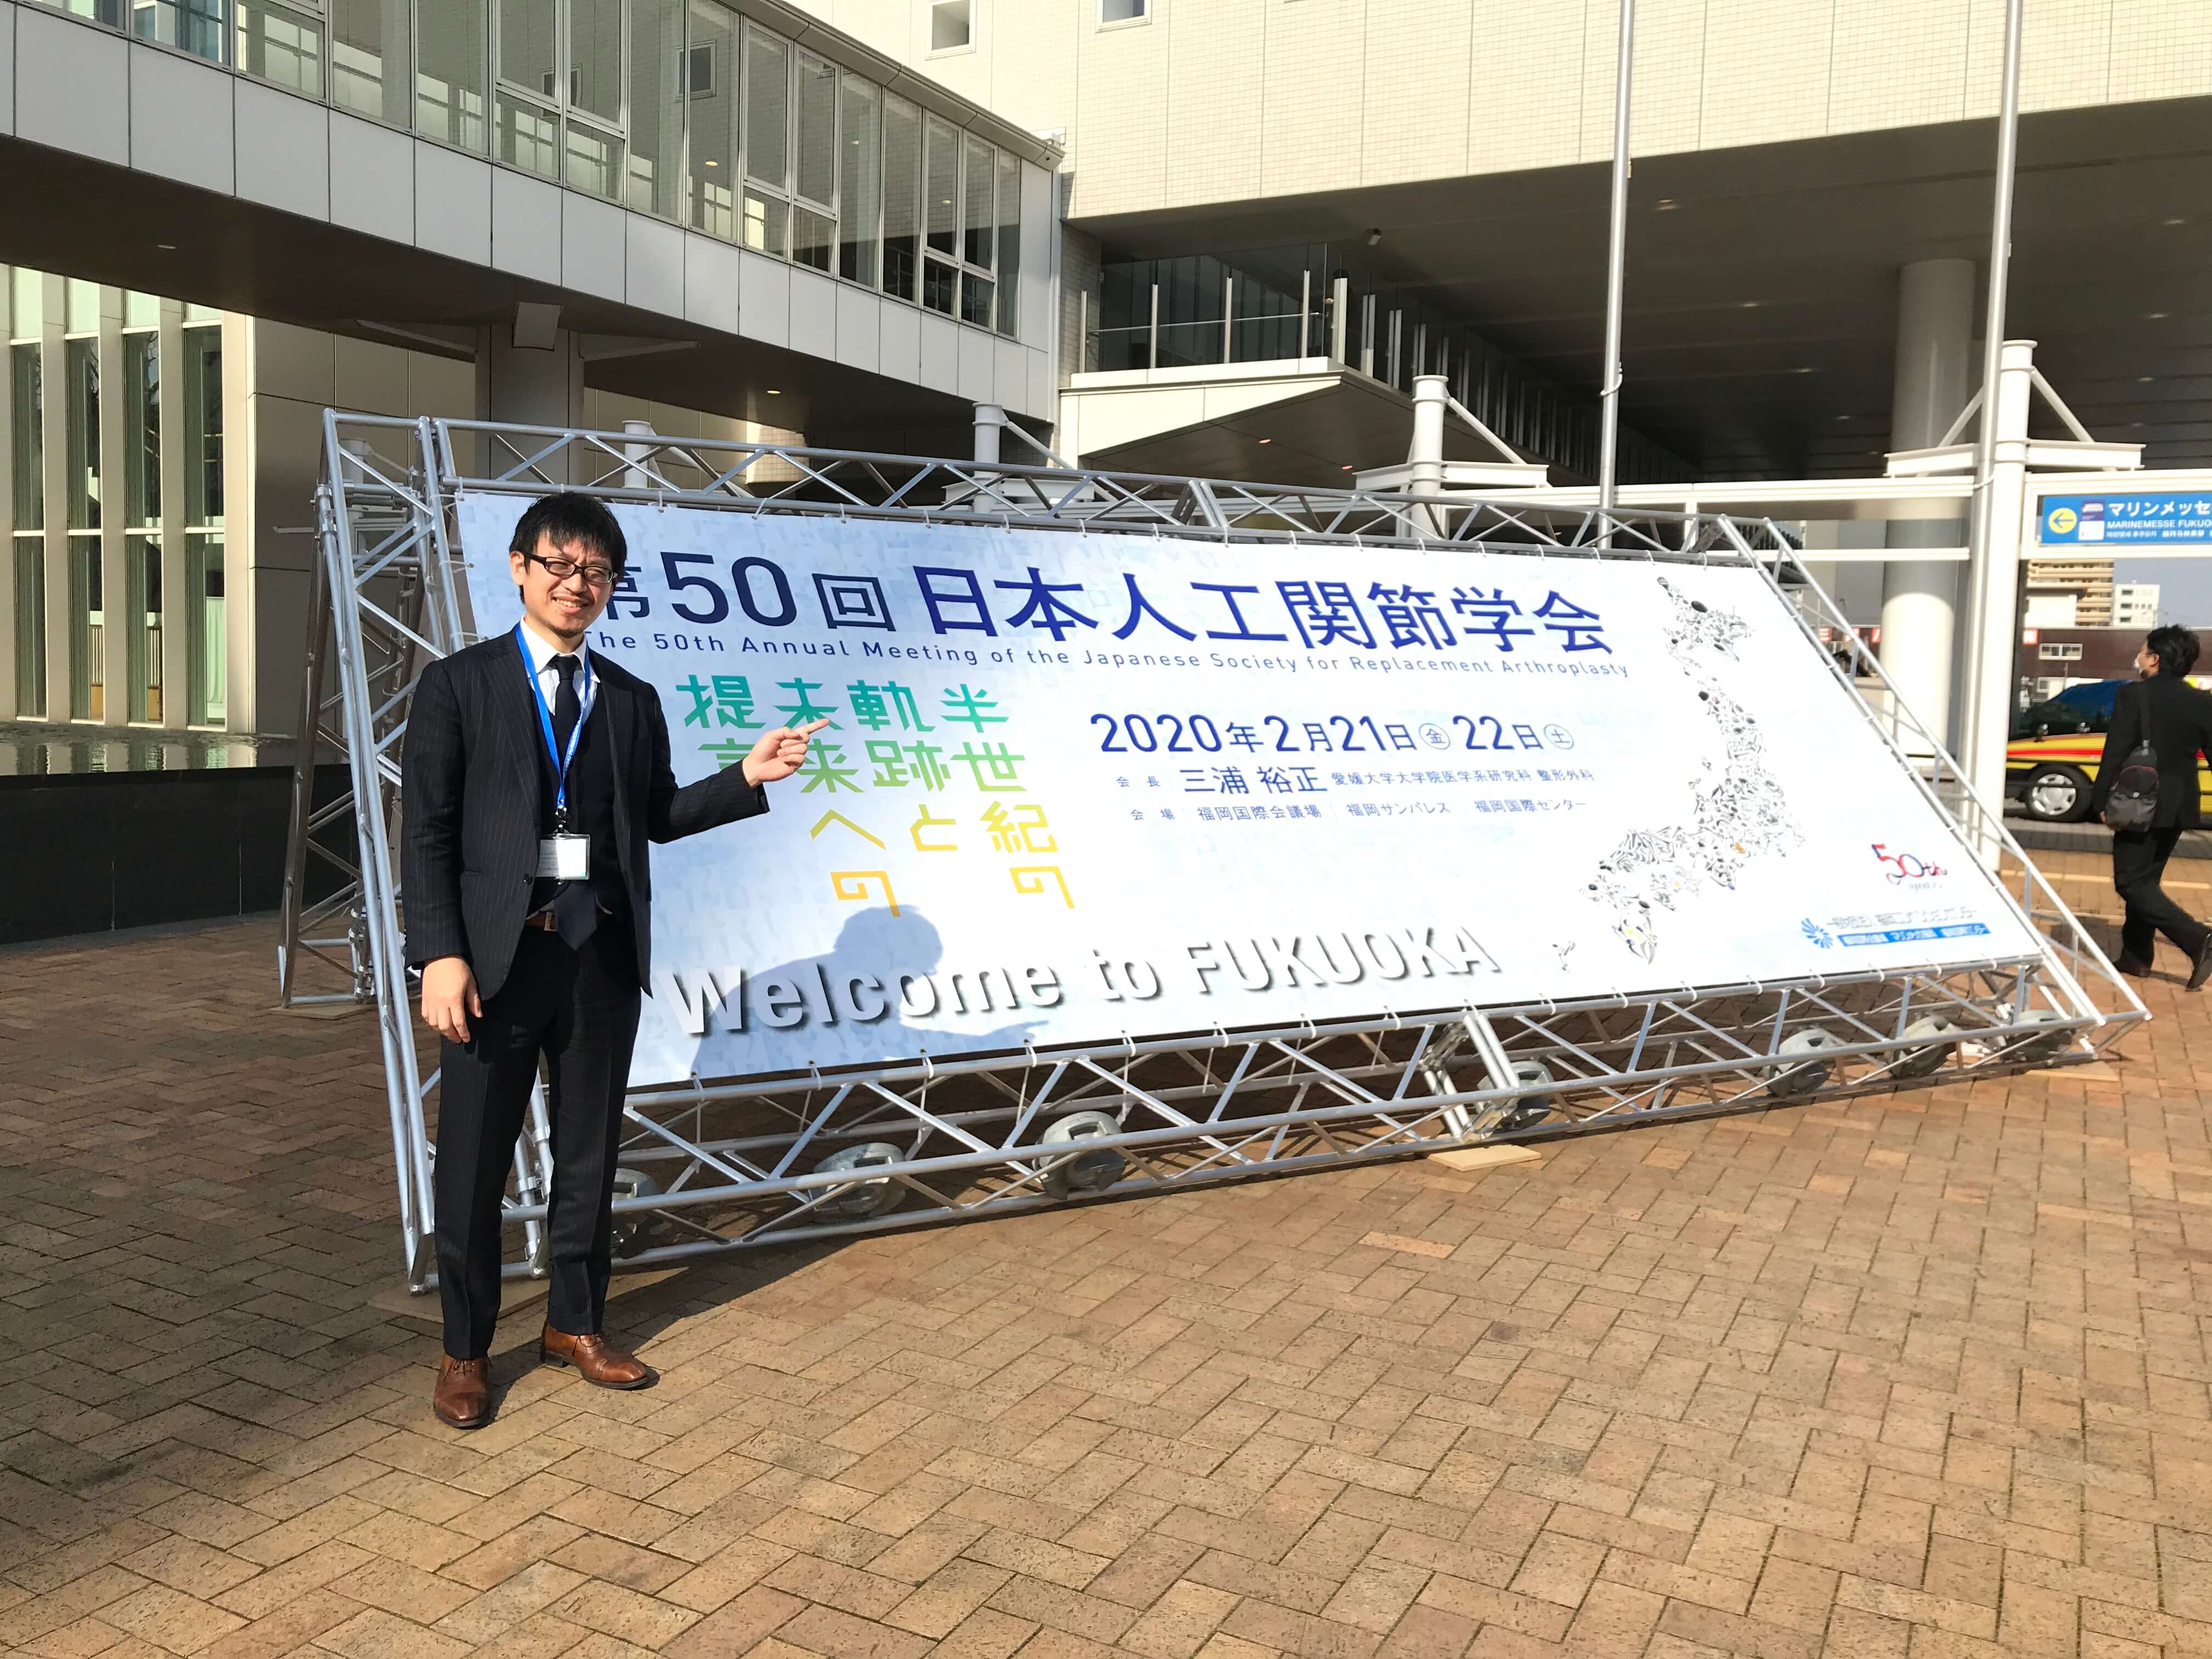

世田谷人工関節・脊椎クリニックの院長の塗山正宏です。

世田谷人工関節・脊椎クリニックの院長の塗山正宏でした。